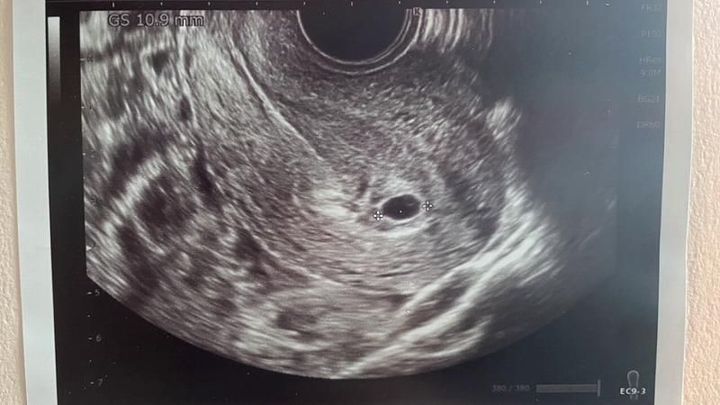

Sitakke

実際のエコー写真 かえでさん提供

「エコー写真で胎嚢を見て、妊娠検査薬の線じゃなくて、赤ちゃんの姿を本当に見て、それで堕ろしたくないなって思って」